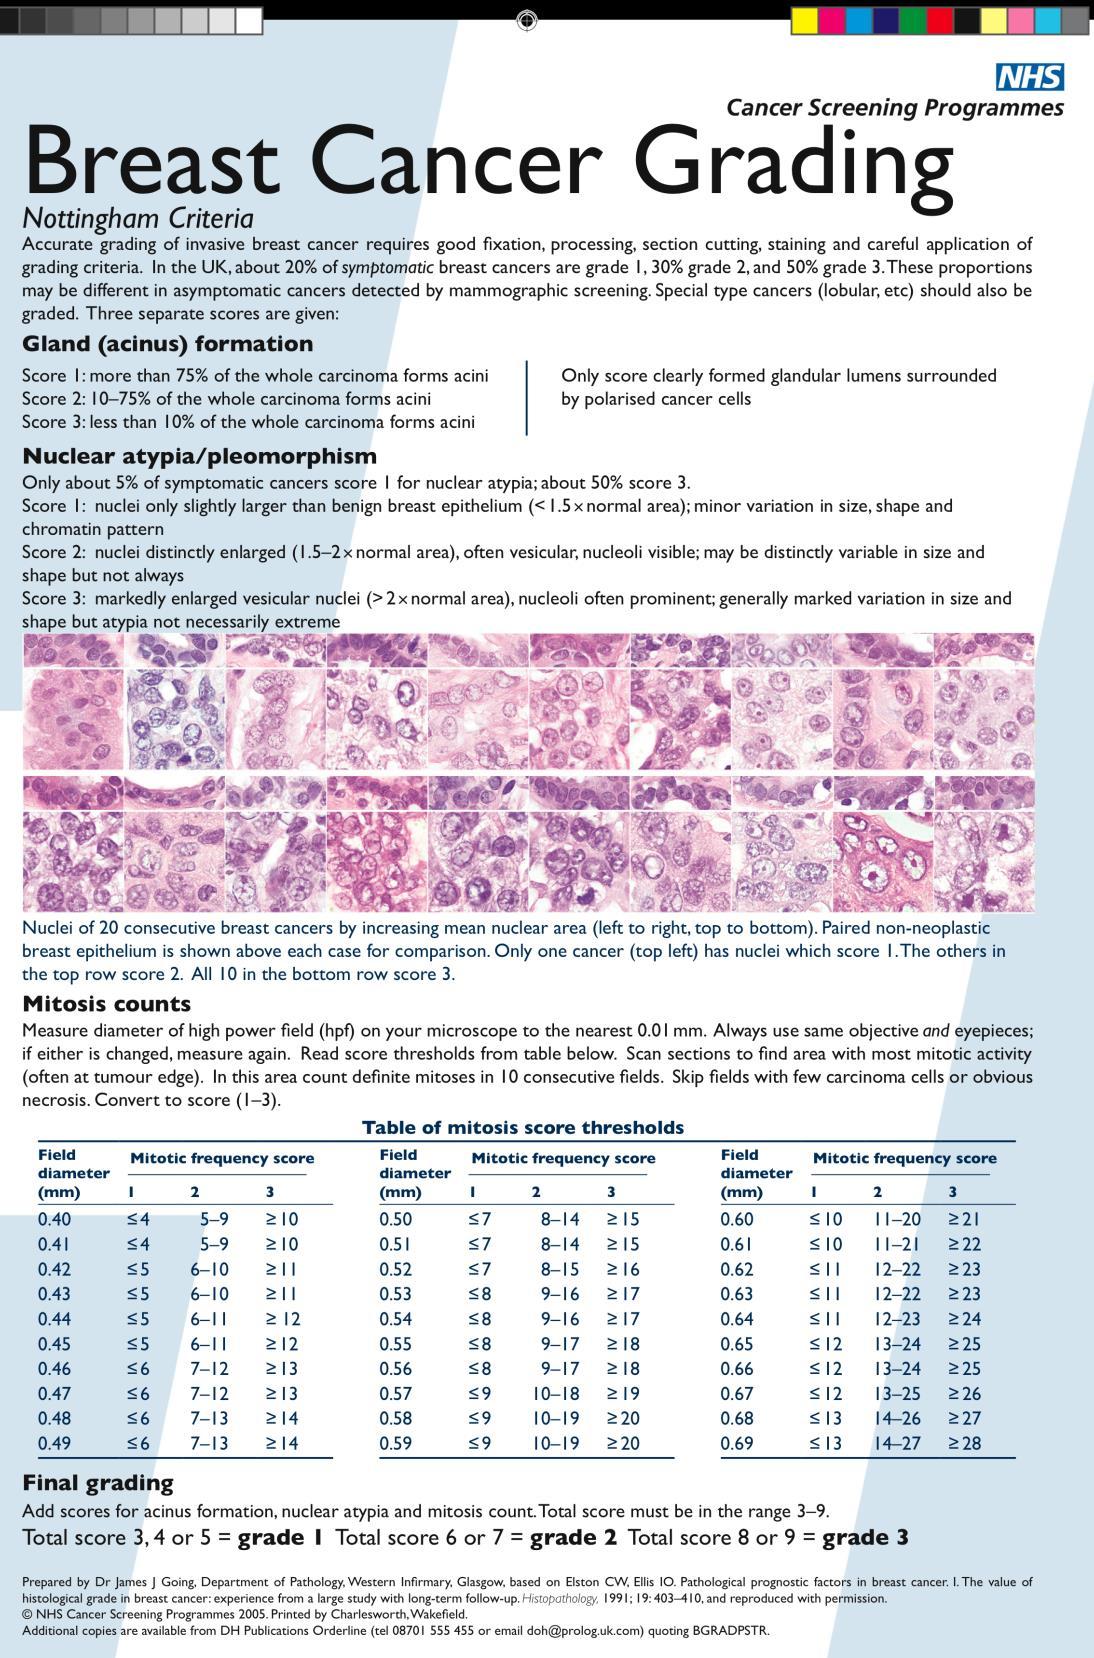

Degree of differentiation of the tumour tissue. Applicable to all the cases Good specimen preparation – a prerequisite! - Thickness of tissue - Volume of fixative - Time - Needle cores 5-6 hours - Larger specimens 12 hours or more

All parts of the tumour are scanned. Clear acinar or gland formation or defined tubular structures with a central luminal space are assessed semi-quantitatively.

Score 1

Score 2

Score 3

1: Nuclei small in size with little increase in size in comparison with normal breast epithelial cells, regular outlines, uniform nuclear chromatin. 2: Cells larger, open vesicular nuclei, visible nucleoli, moderate variation in both size and shape. 3: Vesicular nuclei, prominent nucleoli, marked variation, large bizzare forms.

Mitotic counts

In unselected breast cancer series, the overall survival has been shown to be significantly better in patients with grade I tumours than in those with grade 2/3 tumours. Histological grade has a prognostic value that is equivalent to that of LN status and greater than that of tumour size.